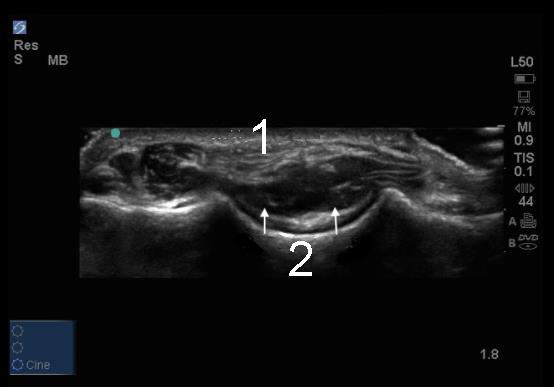

軟骨のある肘後部陥凹の横断画像

三頭筋腱

後陥凹